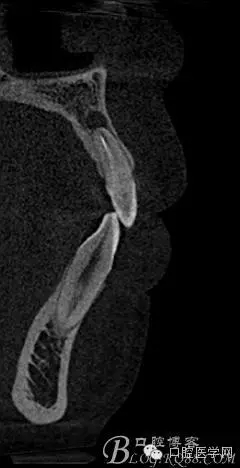

補拍CBCT進行診斷分析

CBCT測量得出根尖囊腫3×4mm,進行常規(guī)根管充填后行根尖切除術(shù)